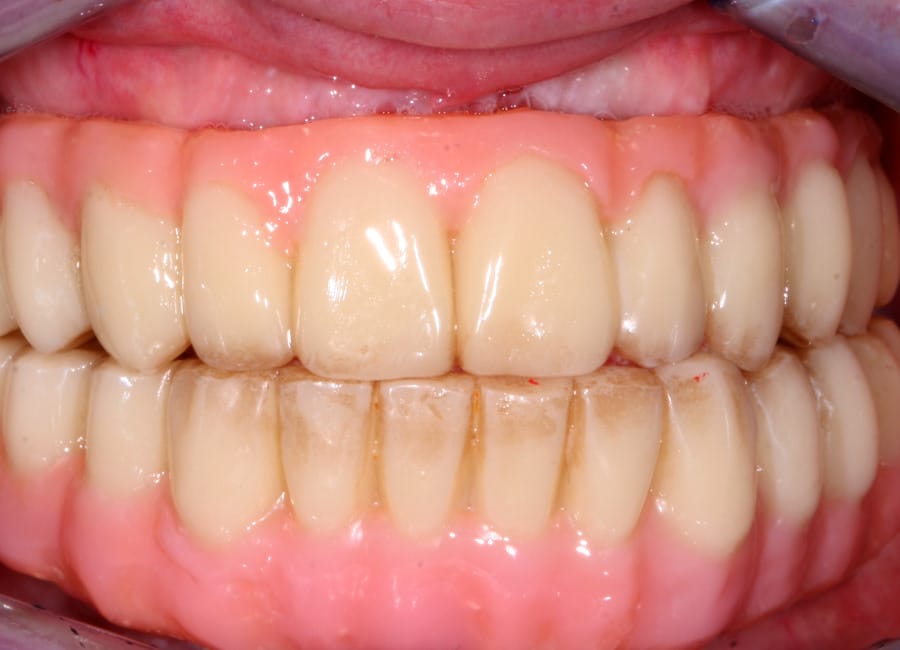

Results

The moment Natalie saw her new smile, the emotion was undeniable. What had once been a source of discomfort, anxiety, and embarrassment had been completely transformed. Her new teeth restored full function and aesthetics, giving her back the ability to eat, speak, and smile without hesitation.

This result was more than cosmetic. It marked the end of a long journey filled with fear and hesitation, and the beginning of a new chapter defined by confidence and well-being. Natalie’s story is a powerful example of how modern dentistry, when led by skilled professionals and supported by cutting-edge technology, can restore much more than teeth.